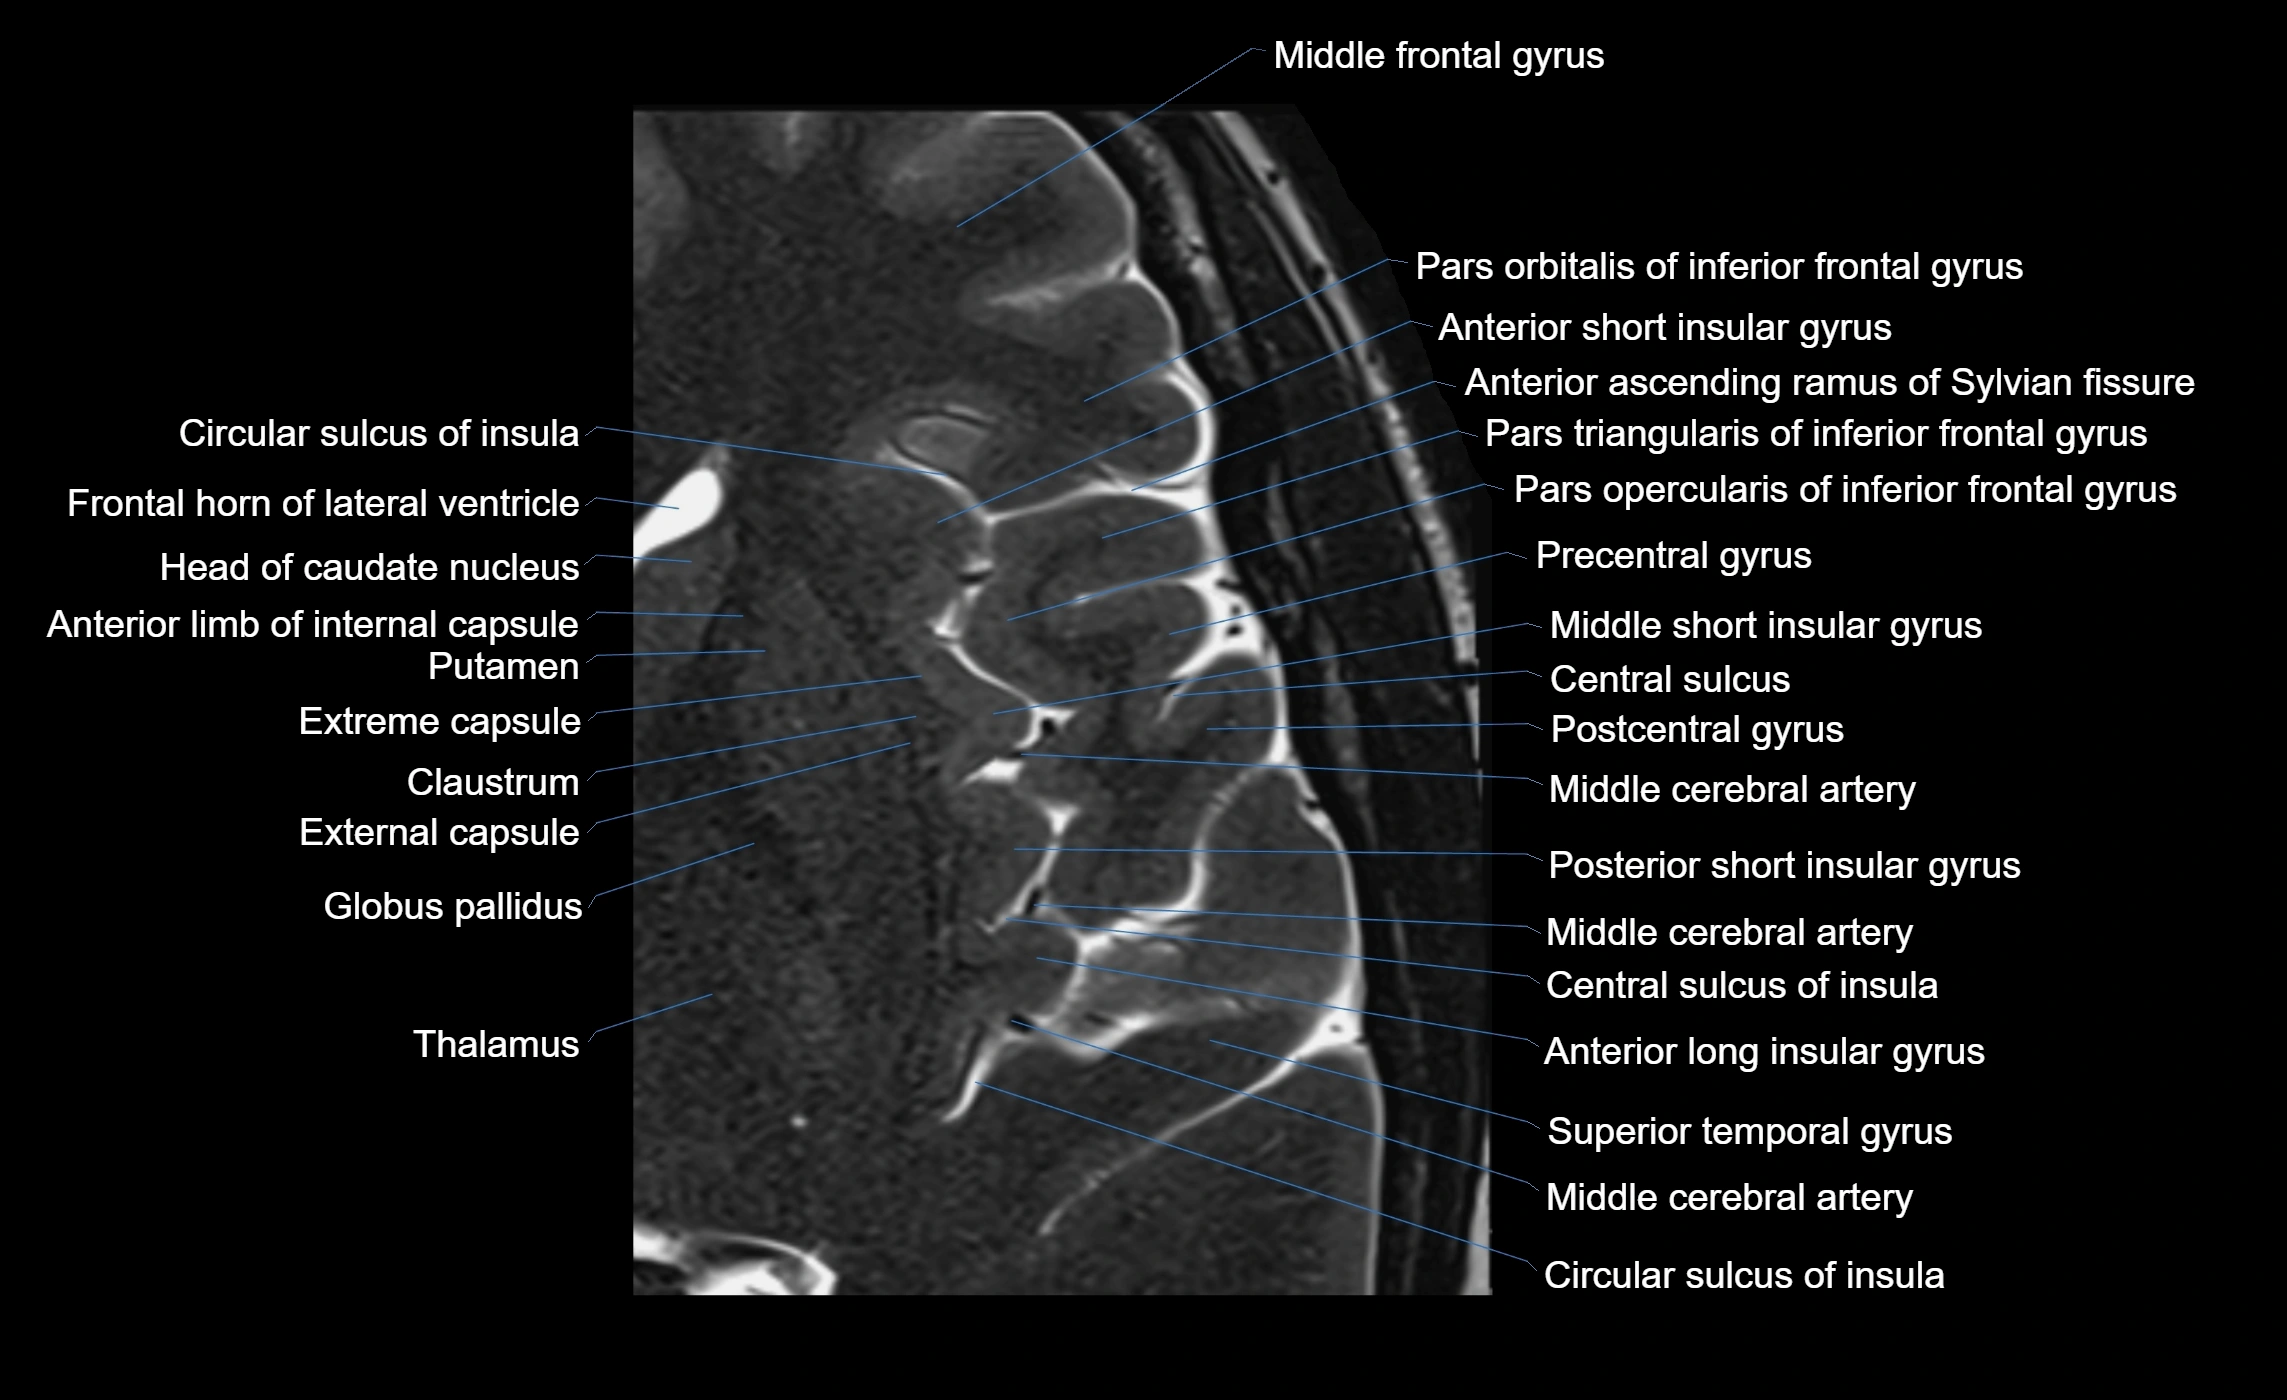

The anterior ascending ramus of the Sylvian fissure is a significant anatomical landmark in the lateral surface of the cerebral hemisphere. It represents one of the key branches of the Sylvian fissure (also known as the lateral sulcus) and plays an essential role in demarcating the boundaries between important cortical regions, notably within the frontal and parietal lobes. Understanding its anatomy and imaging appearance is crucial in neuroradiology, neurosurgery, and neuroanatomy for accurate localization and identification of adjacent brain structures.

• The anterior ascending ramus is a short, superiorly oriented branch that arises from the main stem of the Sylvian fissure.

• It projects upward (anteriorly and slightly dorsally) from the lateral sulcus into the inferior frontal gyrus.

• This ramus separates the pars opercularis (opercular part) from the pars triangularis (triangular part) of the inferior frontal gyrus.

• The anterior ascending ramus marks the boundary between Broca's area and adjacent cortical areas in the dominant hemisphere.

MRI Appearance

• T1-weighted imaging:

• The Sylvian fissure and its anterior ascending ramus appear as low-signal intensity (dark) CSF-filled clefts between the gyri.

• Clear demarcation between adjacent gray and white matter.

• T2-weighted imaging:

• The fissure, including the anterior ascending ramus, is hyperintense (bright) due to CSF signal.

• Better visualization of the separation between opercular and triangular parts of the inferior frontal gyrus.

• FLAIR imaging:

• The ramus is visualized as a linear dark space (suppressed CSF signal) between the surrounding cortex.

• Adjacent cortical and subcortical abnormalities (e.g., edema or gliosis) can be assessed relative to the ramus.

MRI images

image